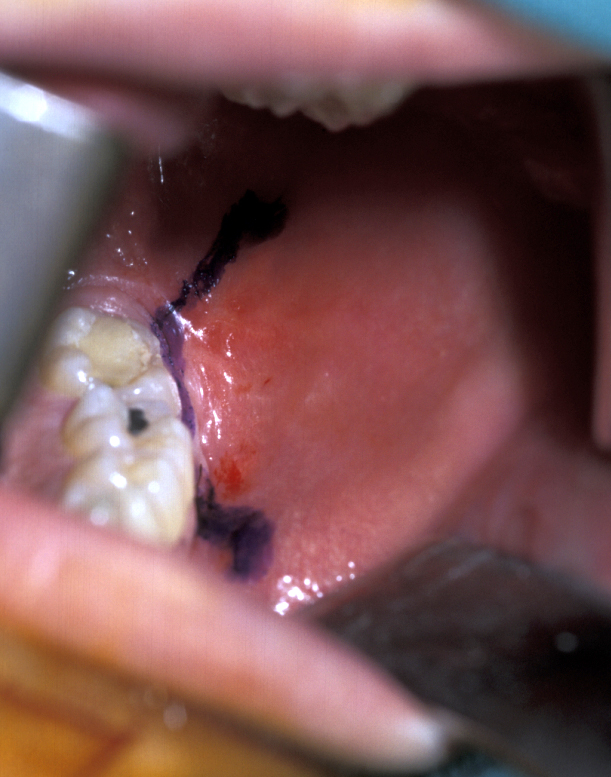

- Buccal Flap – a full thickness mucoperiosteal flap is raised from the buccal surface of the wisdom tooth area. The choice of incision varies, but commonly involves an incision along the external oblique ridge passing forward either around the second molar tooth or out into the buccal sulcus (Figure 3). If little or no bone is to be removed, a simple relieving incision may be all that is necessary. The important point is that dissection proceeds in a subperiosteal plane as this minimises postoperative swelling and trismus (Figure 4).

- Lingual Flap – some authorities do not raise a lingual flap at all. The popularity of this approach was from the days when accurate very high-speed surgical drills were not available and the ‘lingual split bone’ technique was popular in the UK and areas influenced by UK training. Their argument is that it is the process of actually raising the flap that causes injury to the lingual nerve. On the other hand, it is argued that the nerve is at risk from direct trauma from the burr/chisel if it is not retracted. Again, if used, the flap is raised by subperiosteal dissection. Here it is important not to ‘bow-string’ the nerve over the retractor (usually a Howarth’s elevator; Figure 1), but to widely undermine the lingual periosteum to allow the tissues to lie passively and use a wide subperiosteally placed retractor. The elevation of a small cuff of distal attached mucosa is designed for visibility, not for ‘lingual nerve protection’ and is not associated with an increase in morbidity (Figure 5).